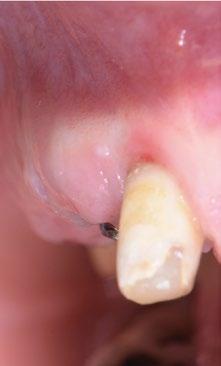

Paciente mujer de 35 años, con amplia exposición gingival en sonrisa y alta demanda estética (Fig. 1, 2).

Su solicitud inicial es volver a blanquear el 21, que había sido previamente endodonciado y había recibido sucesivos tratamientos blanqueadores que habían recidivado. Refiere ligera molestia en la papila interincisiva. En la exploración radiográfica intraoral 1 2

se aprecia una extensa reabsorción radicular interna, con el consiguiente defecto óseo, que se confirma con un CBCT (Fig. 3, 4, 5). Se informa a la paciente del riesgo de fractura espontanea. Esta solicita solucionar el problema antes de que avance más.

En estos casos es crítica la gestión de los tejidos blandos para compensar la pérdida del soporte por parte del trayecto supracrestal de la raíz con en ITC y provisionalización inmediata.